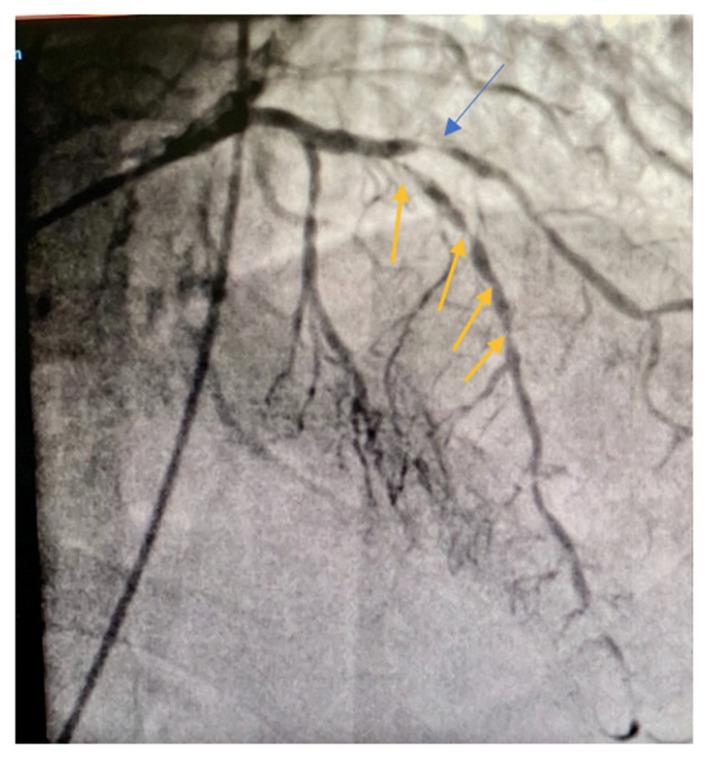

Coronary endarterectomy (CE) emerged as a necessity to achieve complete surgical myocardial revascularization in patients with diffusely diseased coronary arteries and it also serves as aid to coronary bypass grafting (CABG). The safety and postoperative prognosis of this procedure are still matters of debate. There are no clear preoperative indications, a standard technique has not yet been established as gold standard and the postoperative management differs depending on each institution. CE of the left anterior descending artery (LAD) is technically challenging and potentially hazardous with high risk of postoperative myocardial infarction. In this article, we describe the open technique for CE of the LAD with its specific details, which we believe could be the safest and the best reproductible option. To better understand the profile of a patient requiring such a procedure we present the case of a 73-years old male with diffused coronary artery disease (CAD) and a short review of literature.

冠状动脉内膜切除术(CE)成为患有弥漫性冠状动脉疾病患者实现完全手术心肌血运重建的必要手段,并且它也辅助冠状动脉搭桥术(CABG)。该手术的安全性和术后预后仍是有争议的问题。目前尚无明确的术前指征,尚未确立标准技术作为金标准,并且术后管理因各机构而异。左前降支(LAD)的CE在技术上具有挑战性且潜在危险,术后心肌梗死风险高。在本文中,我们描述了LAD的CE开放技术及其具体细节,我们认为这可能是最安全且最具可重复性的选择。为了更好地了解需要进行此类手术的患者情况,我们介绍了一名73岁患有弥漫性冠状动脉疾病(CAD)男性患者的病例,并对文献进行简要回顾。